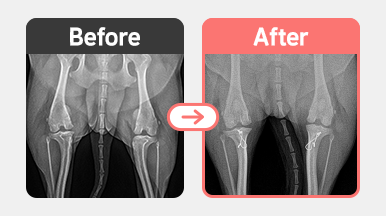

[TPLO 수술] 비숑 / 3살 / 우측 전방십자인대 완전 파열

2025-11-28